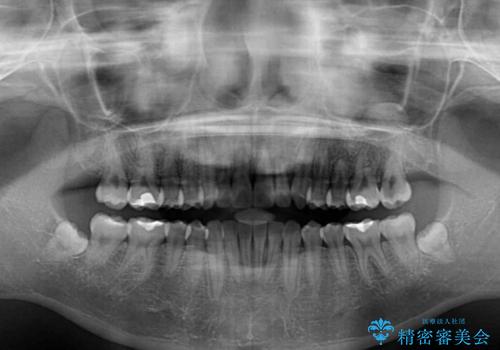

気になる残存乳歯と八重歯 ワイヤー矯正を併用したインビザライン治療

- 八重歯を気にして来院された患者様です。

八重歯のために乳歯が残存していたため、乳歯を抜去して八重歯となっている犬歯を歯列に収めることとしました。

八重歯の移動量が多くなるため、インビザラインと併用してワイヤー矯正を行い、八重歯を改善した後に、上下歯列をインビザラインで整えることとしました。

犬歯は歯根が長くて太いため移動に時間がかかる上に、周囲の歯が八重歯に寄ってきてしまうため、仕上がるまでに期間がかかりました。